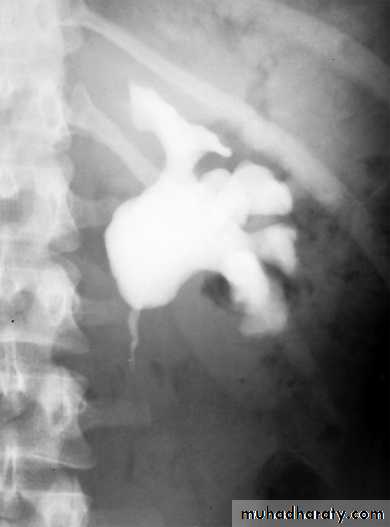

Intravenous urography (IVU): reveals hydronephrosis and its level and may also show the underlying cause. It requires good preparation and the injection of a contrast material which may cause allergy.

IVU Showing unilateral (left) hydronephrosis - PUJOIVU Showing unilateral (right) hydroureteronephrosis